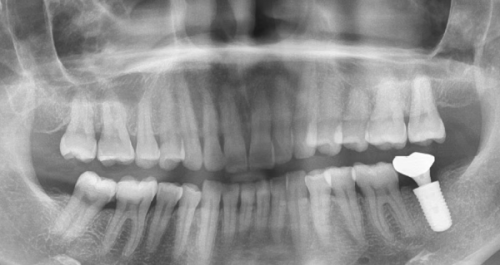

有个52岁的王先生,为了省钱选择了一家低价诊所做种植牙。结果术后三年,他的下唇仍然没有知觉,生活受到了较大影响。所以,为了避免神经损伤,术前一定要拍摄CBCT三维影像,确保种植体与神经管保持2mm以上的安心距离。

糖尿病患者和吸烟者是感染的高危人群。当糖尿病患者的糖化血红蛋白>7%时,感染风险会激增3倍;每天吸烟超过10支的人,骨结合失败率会升高2.5倍。曾经有一位患者,术后忽视了口腔清洁,在CT片上都能看到骨吸收形成的空洞。所以,手术前后一定要注意消毒和清洁,尤其是高危人群更要格外小心。